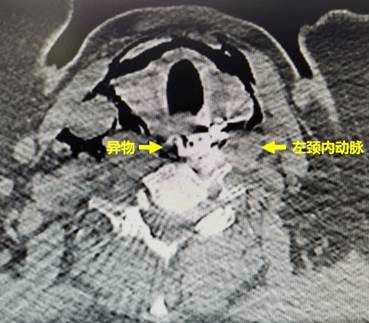

64岁的女性陈某,因误食异物(假牙)后喉部疼痛、呼吸困难,被120急救车紧急送往哈医大一院急诊急救中心。胸外科常浩教授为患者检查发现异物形状特殊、位置刁钻,并且固定假牙的钢钩已刺破食管壁,引起纵隔感染,患者随时面临窒息风险。同时,钢钩毗邻左颈内动脉,随时有刺破颈部血管,导致大出血的风险,患者的生命悬于一线。